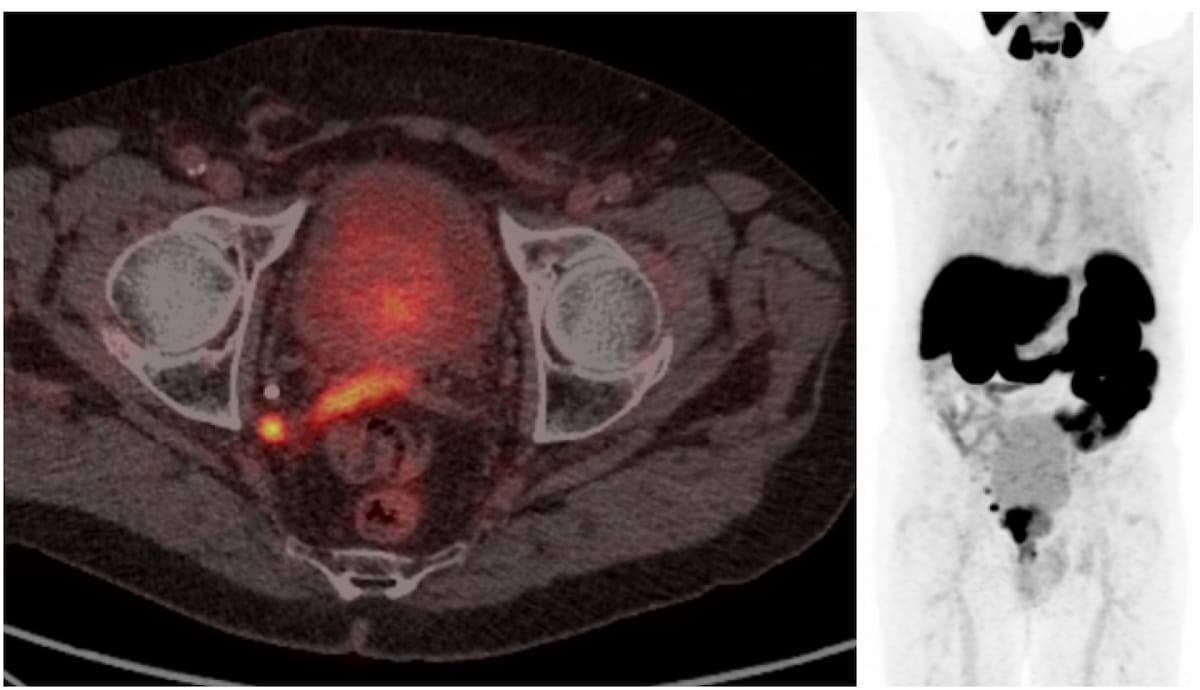

Here one can see radiotracer accumulation in a metastatic pelvic sidewall lymph node and right seminal vesicle uptake (left). In addition to these findings, the maximum intensity projection (MIP) view shows radiotracer accumulation in the prostate tumor. (Images courtesy of the European Congress of Radiology.)